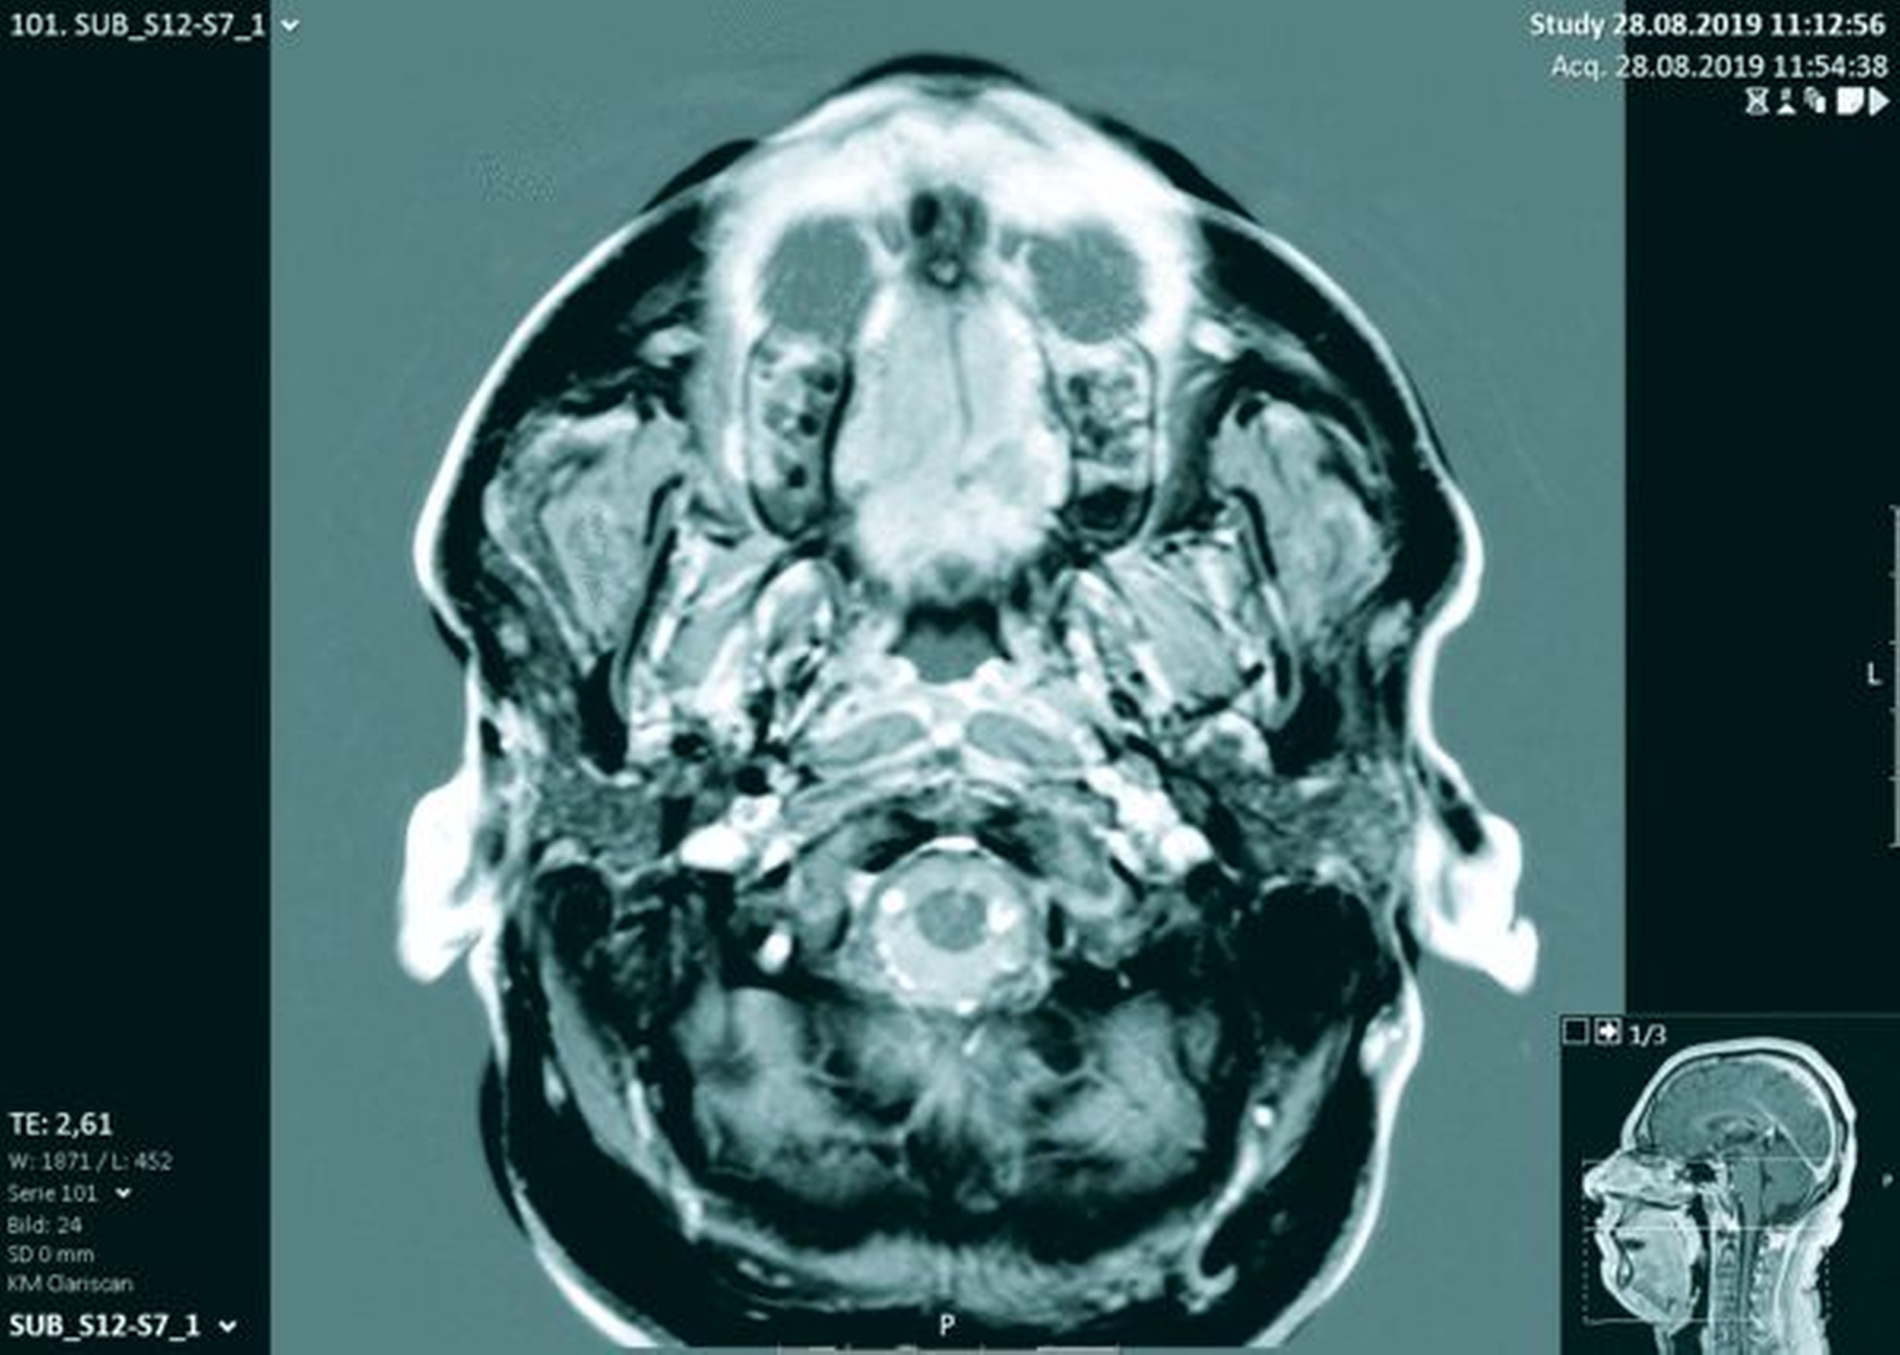

Zur weiteren Diagnostik und zur Beurteilung der Ausbreitung und der Infiltration des Befunds wurde eine Magnetresonanztomografie (MRT) durchgeführt. Hier zeigte sich eine submukosal gelegene, 8 mm x 10 mm x 8 mm große, glatt begrenzte, T1 hypertense, T2 inhomogen teils hypointense, teils isointense Raumforderung mit deutlichem Signalabfall in T2-Fettsättigung (Abbildung 2). Es bestand kein Hinweis auf knöcherne Infiltration. Daher wurde der Befund mit einem Sicherheitsabstand von 1 bis 2 mm unter Schonung des Nervus und der Arteria palatina major bis auf den palatinalen Knochen reseziert (Abbildung 3).